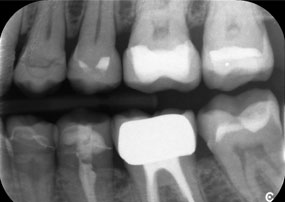

Ein weiteres Beispiel für die klinische Leistungsfähigkeit der Power Edition war der Austausch einer beschädigten Zirkonkrone bei einer 63-jährigen Patientin. Diese stellte sich aufgrund eines abgesplitterten Verblendungsteils ihrer 20 Jahre alten Zirkonkrone an Zahn 6 vor. Trotz der Position im Seitenzahnbereich empfand die Patientin dies als störend und wünschte eine neue Krone.

Die Power Edition ermöglichte eine präzise Schnittführung, wobei das erhöhte Drehmoment und die verbesserte Kühlung dazu beigetragen haben, die Krone ohne größeren Materialverlust zu entfernen. Das Spannsystem und das verbesserte Drehmoment erwiesen sich hierbei als essenziell.